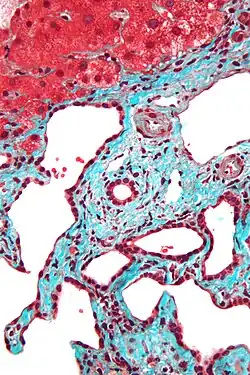

Micrograph of a bile duct hamartoma. Trichrome stain, high magnification

Micrograph of a bile duct hamartoma. Trichrome stain, high magnification -